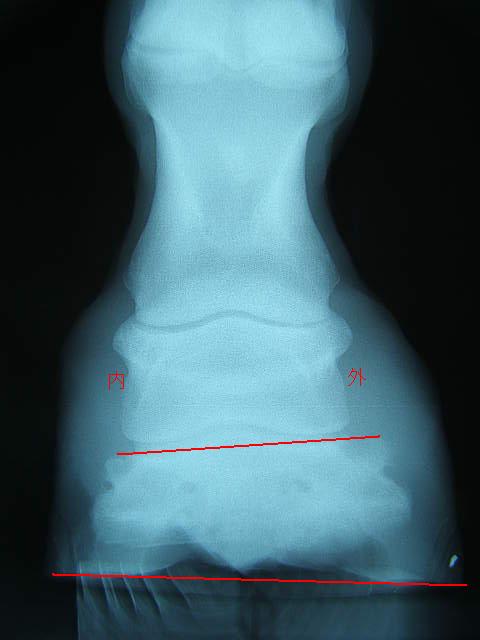

9月の右前肢

こちらも蟻洞がなくなりました。

順調に改善しているのが確認できて本当にホッとしました〜